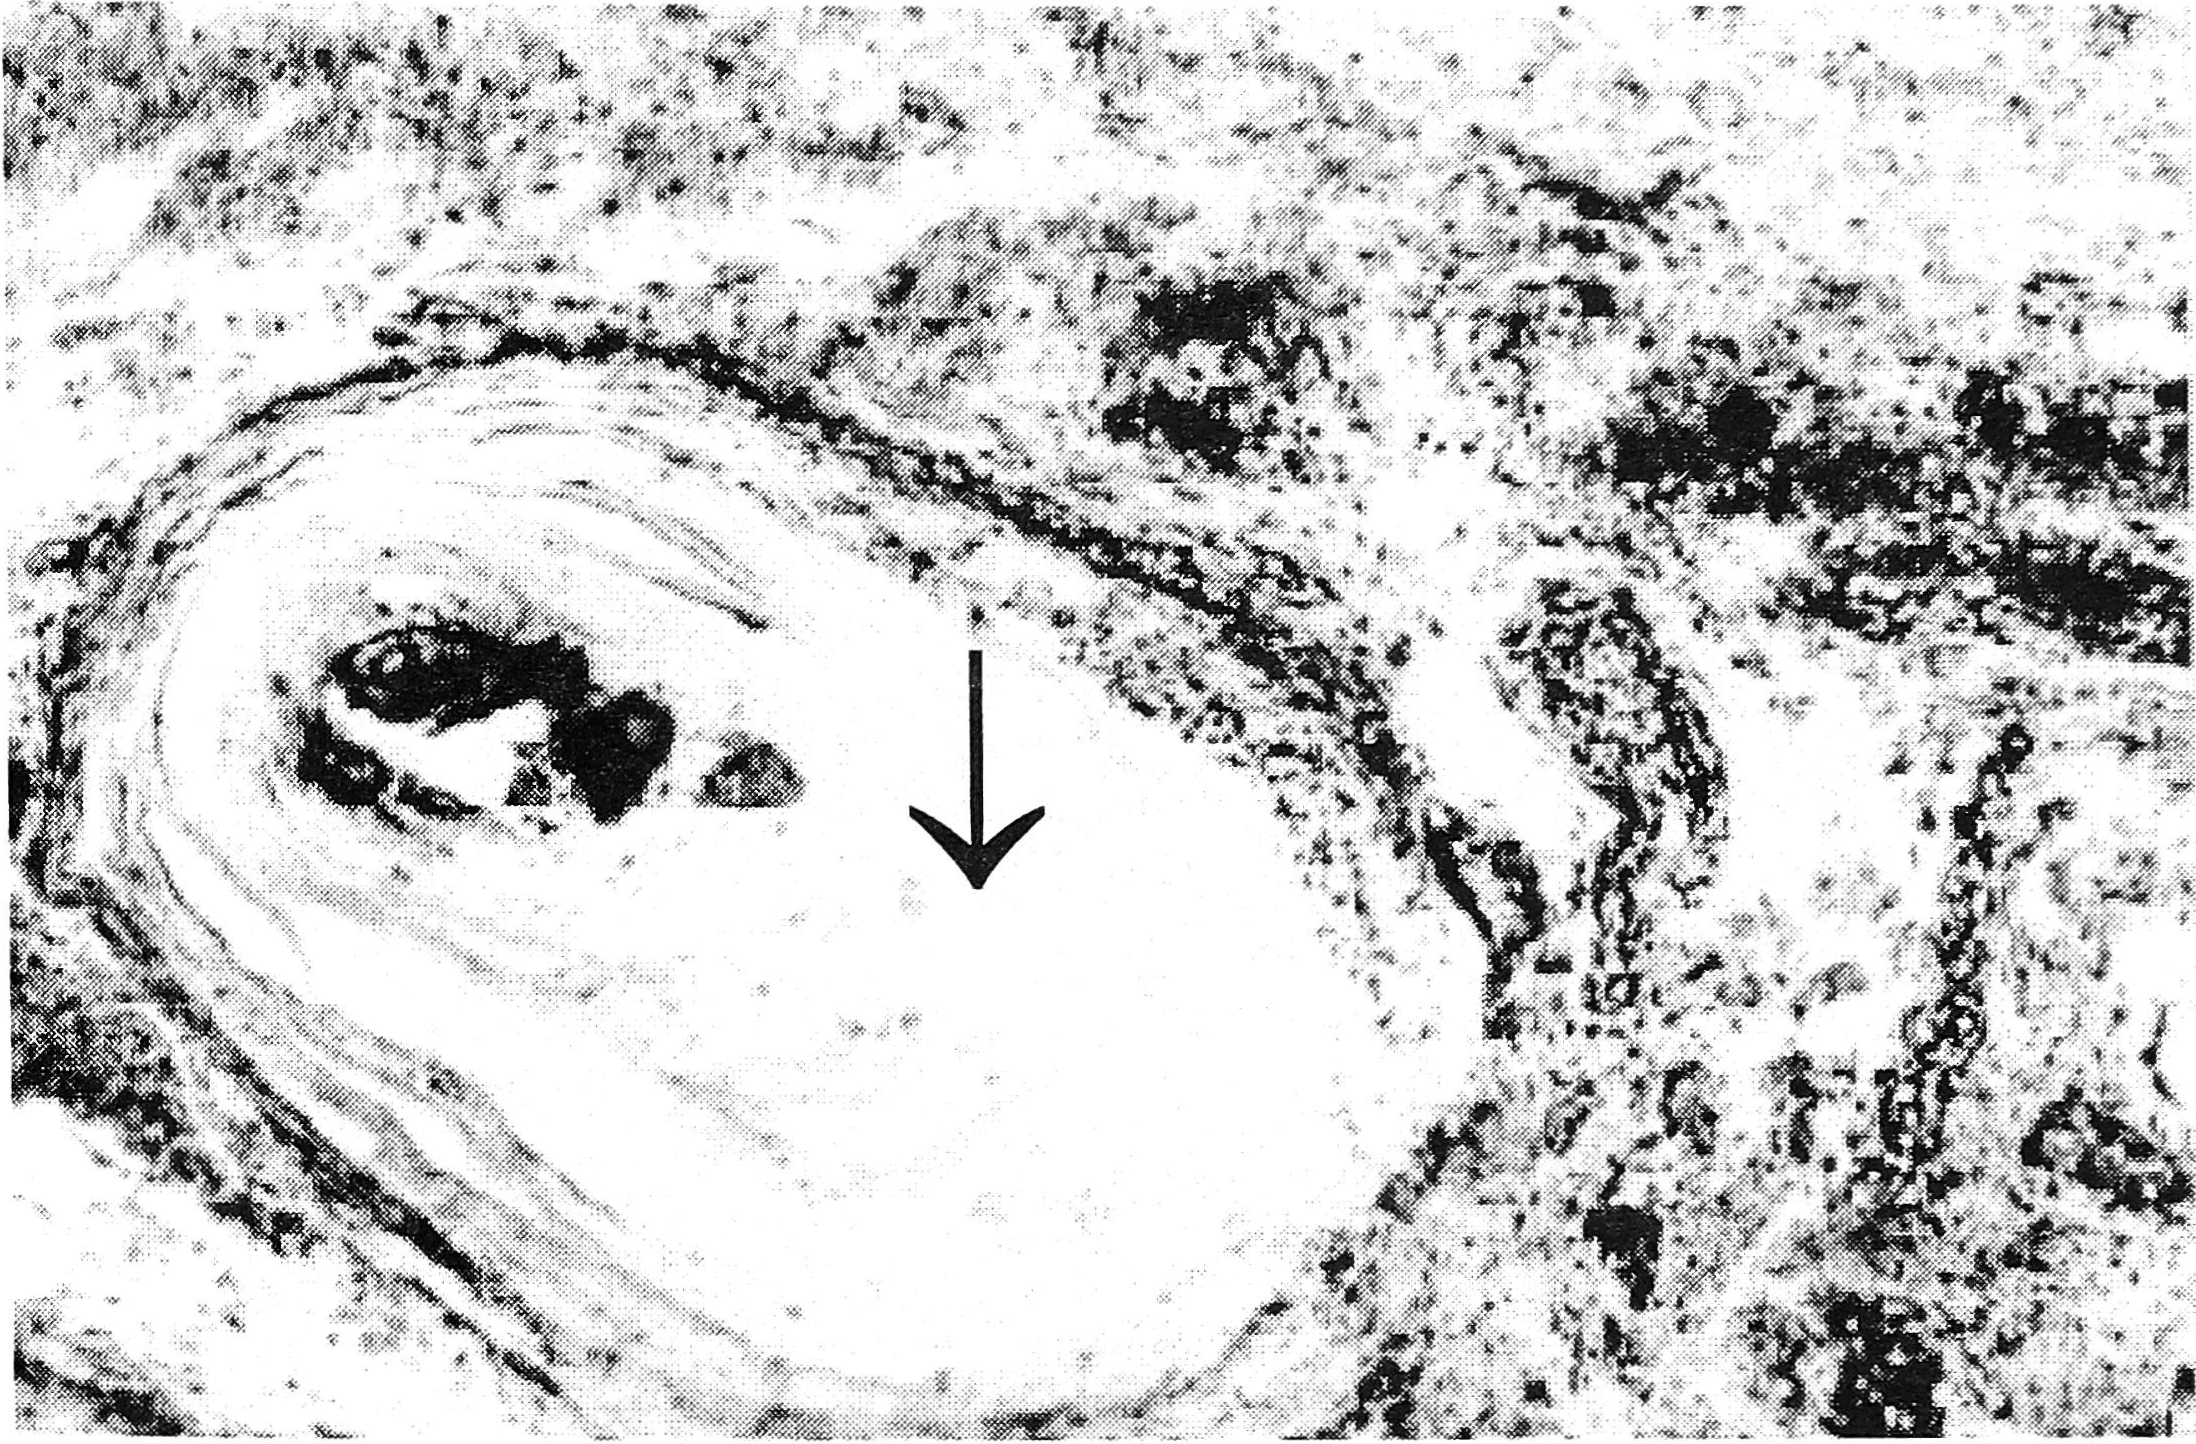

При гистологическом исследовании удаленного фрагмента стенки маточной трубы были выявлены склеротические изменения в строме ворсин слизистой и в мышечной оболочке (см. рис. 1). Кроме того, в мышечной оболочке найдены множественные петрификаты, а также яйца гельминтов (см. рис.2). Яйца имели характерную овоидную форму, размеры до 0,17x0,08 мм, были окружены зоной гиалинизированной ткани с немногочисленными макрофагами по периферии. Часть яиц была обызвествлена. На этом основании диагностирован мочеполовой шистосоматоз.

Рис. 1. Склеротические изменения в стенке маточной трубы (см. стрелку). Окраска гематоксилином и эозином, ув. х100.

Рис. 2. Обызвествленные яйца шистозом в стенке маточной трубы образуют конгломерат, окруженный гиалинизированной фиброзной тканью - так называемые «песчаные пятна» (см. стрелку). Окраска гематоксилином и эозином, ув. х100.

Именно это рубцевание лежит в основе характерного для моче- полового шистозоматоза, деформирующего стенку органа диффузного и очагового фиброза. Обызвествленные яйца шистосом образуют крупные конгломераты, окруженные гиалинизированной соединительной тканью (так называемые «песчаные пятна»), которые были обнаружены в данном наблюдении в стенке маточной трубы. По данным H.M.Gilles (1987) [3], хронический сальпингит с сужением просвета маточных труб, не специфическое воспаление и гранулематоз яичника с исходом в склероз являются типичными для мочеполового шистозоматоза. В резецированных участках яичников в нашем наблюдении патологии не выявлено.